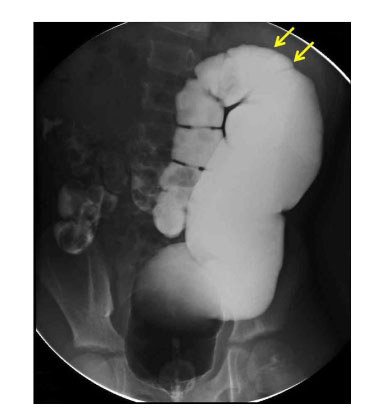

Fig. 1

Barium enema shows dilated rectosigmoid colon with abrupt transition to a normal proximal colon.

Fig. 1 Barium enema shows dilated rectosigmoid colon with abrupt transition to a normal proximal colon.